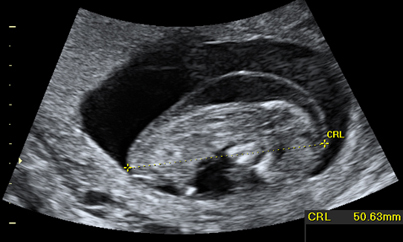

Ecografía de primer trimestre que muestra pliegue nucal patológico.